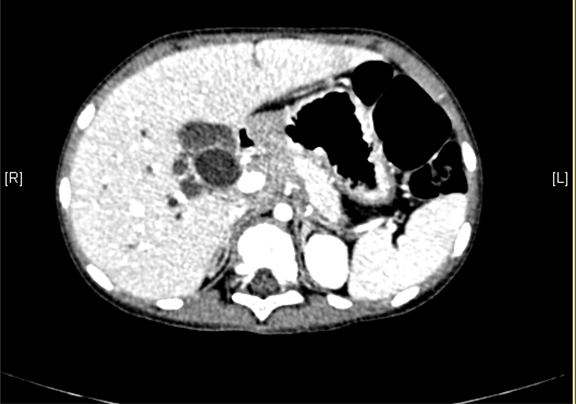

上腹部增强CT:肝内外胆管扩张,考虑先天性胆管扩张症可能性大。

术前CT检查:

动脉期

静脉期

平衡期